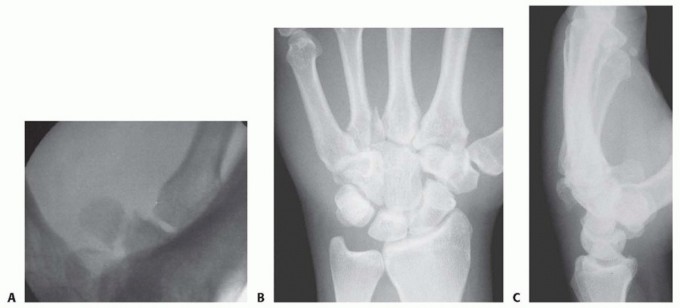

Imaging is the cornerstone of preoperative templating. Routine evaluation begins with high-quality posteroanterior, lateral, and oblique radiographs of the wrist. However, standard views are notoriously inadequate for isolating specific carpal pathology due to osseous overlap. Special radiographic projections are therefore essential. The carpal tunnel view is critical for evaluating the hamate hook and the trapezial ridge. The "papillon view"—a supinated oblique lateral projection with the wrist in radial deviation and the thumb abducted—is highly specific for profiling the hamate hook. Similarly, a 45-degree supinated lateral view optimally visualizes the pisotriquetral articulation.

Image

Despite optimal plain radiography, advanced imaging is frequently required. High-resolution computed tomography (CT) scanning with fine axial, coronal, and sagittal reconstructions has become the gold standard and the imaging modality of choice for complex carpal trauma. CT scans definitively confirm occult fractures, delineate intra-articular comminution, and reveal subtle associated injuries missed on plain films. They allow the surgeon to mentally construct a 3D model of the fracture, facilitating precise preoperative templating of screw trajectories and implant sizes. If dynamic instability is suspected but unconfirmed, an Examination Under Anesthesia (EUA) combined with real-time fluoroscopy (utilizing stress and distraction views) is performed immediately prior to the definitive procedure to finalize the surgical blueprint.